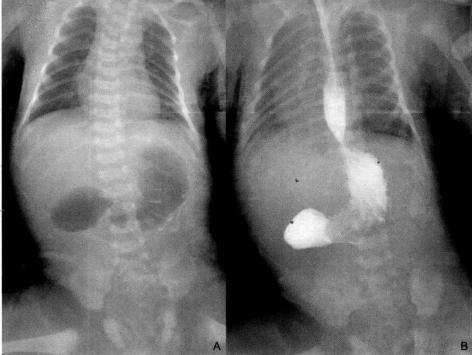

1.腹部平片表现 :可见“双泡征”,为扩张的胃泡 及十二指肠近端影。十二指肠以下肠腔内无气体影 。经胃管注入造影剂行上消化道造影即可 显示十二指肠闭锁部位呈盲管状.可确定诊断。如下图: